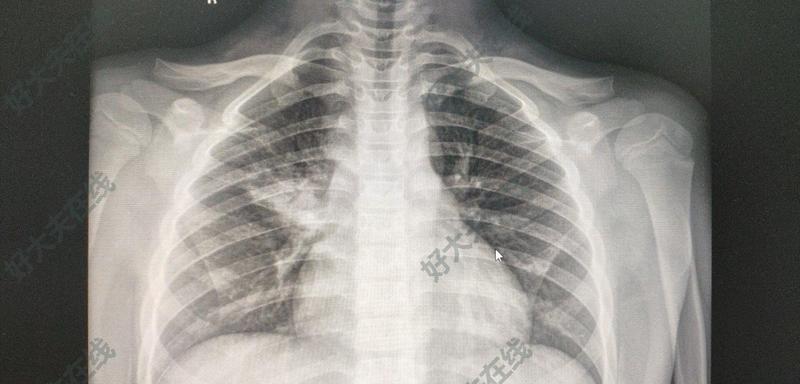

大叶性肺炎

小儿大叶性肺炎,面积挺大,哪里看比较好

肺炎按病理累及的部位分为大叶性肺炎、支气管肺炎和间质性肺炎。大叶性肺炎是指肺炎的病灶累及一个肺段以上的肺炎。由于炎症累及的面积比较大,因此症状比较明显,病情相对比较重,治疗的疗程也相对较长。实际上,现在由于大量强效抗生素的使用,典型的大叶性肺炎已较少见到。大叶性肺炎致病菌有很多种,绝大多数是肺炎链球菌,Ⅲ型肺炎链球菌致病力最强。这种细菌其实是人体口腔和鼻咽部的正常寄生菌,当人体出现免疫力下降或者呼吸道对细菌排出能力下降时,就会引起疾病。在淋雨、过度疲劳、感冒、醉酒等诱因下,或者由于其他疾病引起免疫功能低下时,呼吸道防御功能被削弱,细菌侵入肺泡,通过变态反应使肺泡壁毛细血管通透性增强,浆液及纤维素渗出,渗出物中细菌迅速大量繁殖,并通过肺泡孔及细支气管向邻近肺组织蔓延。大叶性肺炎临床症状大叶性肺炎多发生于青壮年,或者较大的儿童,季节交替以及春冬季节比较多见。春节期间,来门诊就诊的肺部感染病人明显增多,部分为大叶性肺炎。就是因为春节期间天气寒冷,空气质量差,过度劳累及饮酒后免疫力低下所致。大叶性肺炎通常表现为起病急,突发畏寒寒战、高热、胸痛、咳嗽、部分人会咳铁锈色痰液,部分儿童患者会出现食欲不振、疲乏、烦躁,甚至呼吸困难。实际上大叶性肺炎比较好诊断,门诊拍胸片或者胸部CT就可明确,抽外周血查血常规提示白细胞及中性粒细胞明显升高。痰涂片中可以发现革兰氏阳性球菌。血培养及痰培养可以发现肺炎球菌生长。大叶性肺炎的治疗如今抗生素不断的更新换代,广谱抗生素越来越多,对于大叶性肺炎,一经诊断应立即开始治疗,不必等待细菌培养结果。对肺炎球菌性肺炎,青霉素G为首选。还可使用头孢菌素类,如头孢噻吩、头孢唑肟等;氟喹诺酮类药物,如氧氟沙星、环丙沙星。抗菌药物疗程一般为7-10天,或在退热后3天停药。除此之外,需要对症处理发热、疼痛、咳嗽等症状。少数儿童病情可能会比较重,出现中毒性脑病甚或出现感染性休克,需要警惕,尽早的抗感染、抗休克,维持水、电解质平衡。

肺炎通常指肺的急性渗出性炎症,是呼吸系统的常见病、多发病。根据病因不同,由各种生物因子引起的肺炎分别成为细菌性肺炎、病毒性肺炎、支原体肺炎、真菌性肺炎和寄生虫性肺炎;由不同病理因素引起的肺炎,又分别称为放射性肺炎、类脂性肺炎和吸入性肺炎或过敏性肺炎等。根据肺部炎症发生的部位,如发生于肺泡者称肺泡性肺炎,发生于肺间质者称间质性肺炎。根据病变累及范围,又可称为大叶性肺炎、小叶性肺炎和节段性肺炎。按病变的性质又可分为浆液性、纤维性、化脓性、出血性、干酪性及肉芽肿性肺炎等。本文将对细菌性肺炎、病毒性肺炎及支原体肺炎的病因病机及病理表现进行简单论述(一)细菌性肺炎1.大叶性肺炎:是主要由肺炎链球菌引起的以肺泡内弥漫性纤维素渗出为主的炎症,病变通常累及肺大叶的全部或大部。本病多见于青壮年,临床起病急,主要症状为寒战高热、咳嗽、胸痛、呼吸困难和咳铁锈色痰,肺实变体征及外周血白细胞增多等。一般经5-10天体温下降,症状和体征消退。病因和发病机制 大叶性肺炎90%以上由肺炎链球菌引起,其中1、3、7和2型多见,但3型毒力最强。此外,肺炎杆菌、金黄色葡萄球菌、流感嗜血杆菌、溶血性链球菌也可以引起,但均为少见。肺炎链球菌存在于正常人鼻咽部,带菌的正常人常是本病的传播源。当受寒、酗酒、疲劳和麻醉时,呼吸道的防御功能减弱,机体体抗力降低,易致细菌侵入肺泡而发病。进入肺泡内的肺炎菌迅速生长繁殖并引发肺组织的变态反应,(导致肺泡间隔毛细血管扩张、通透性升高,浆液和纤维蛋白原大量渗出并与细菌共同通过肺泡间孔或呼吸性细支气管向邻近组织蔓延,波及部分或整个肺大叶,而肺大叶之间的蔓延则是通过叶支气管播散所致)病理变化及临床病理联系 大叶性肺炎的主要病理变化为肺泡腔内的纤维素性炎,常发生于单侧肺,多见于左侧或右肺下叶,也可同时或先后发生于两个或多个肺叶。典型的自然发病过程大致可分为四期:(1) 充血水肿期:发病的第1-2天,病变肺叶肿胀,暗红色。镜下见肺泡间隔内毛细血管弥漫性扩张充血,肺泡腔内有多量的浆液性渗出液,其内混有少量的红细胞、中性粒细胞和巨噬细胞。渗出液中常可检出肺炎链球菌。此期病人因毒血症而寒战、高热及外周血白细胞计数升高。胸部X线检查显示片状分布的模糊阴影。(2) 红色肝样变期:一般发生于病后的第3-4天,肿大的肺叶充血呈暗红色,质地变实,切面灰红,似肝脏外观,故称红色肝样变期。镜下见肺泡间隔内毛细血管仍处于扩张充血状态,而肺泡腔内则充满纤维素及大量红细胞,其间夹杂少量中性粒细胞和巨噬细胞。其中纤维素丝连接成网并穿过肺泡间孔与相邻肺泡内的纤维素网相联。此期渗出物中仍能检出多量的肺炎链球菌。X线检查可见大片致密阴影。若病变范围较广,患者动脉血中氧分压因肺泡换气和肺泡通气功能障碍而降低,可出现发绀等缺氧症状,肺泡腔内的红细胞被巨噬细胞吞噬、崩解后,形成含铁血黄素随痰液咳出,致使痰液成铁锈色。病变波及胸膜时则引起纤维素性胸膜炎,发生胸痛,并可随呼吸和咳嗽而加重。(3) 灰色肝样变期:发病后的第5-6天,病变肺叶仍肿大,但充血消退,由红色逐渐转变为灰白色、质实如肝,故称灰色肝样变期,镜下见肺泡腔内渗出的纤维素增多、相邻肺泡纤维素丝经肺泡间孔相互连接的现象更为多见,纤维素网中有大量中性粒细胞,因肺泡壁毛细血管受压迫,肺泡腔内几乎很少见到红细胞。此期肺泡虽仍不能充气,但病变肺组织内因肺泡间隔毛细血管受压,充血量显著减少,使静脉血氧含量不足反而减轻,故缺氧状况得以改善。患者的其他临床症状开始减轻,咳出的铁锈色痰逐渐转变为粘液浓痰。渗出物中治病菌除被中性粒细胞吞噬杀灭外,此时机体的特异性抗体业已形成,故不易检出细菌。(4) 溶解消散期:发病后1周左右进入该期。此时机体的防御功能显著增强,病菌消灭殆尽。肺泡腔内中性粒细胞变性坏死,并释放出大量蛋白水解酶将渗出物中的纤维素溶解,由淋巴管吸收或经气道咳出。肺内实变病灶消失,病变肺组织质地较软。肺内的炎症病灶完全溶解消散后,肺组织结构和功能恢复正常,胸膜渗出物亦被吸收或机化。病人体温下降,临床症状和体征逐渐减轻、消失,或胸部X线检查恢复正常。此期约历时1-3周。大叶性肺炎的上述病理变化是一个连续的过程,彼此无绝对界限,同一病变肺叶的不同部位亦可呈现不同阶段的病变,现今常在疾病早期即开始对病人使用抗菌素类药物,干预了疾病的自然经过,故已很少见到典型的四期病变过程,病变常变现为阶段性肺炎,病程也明显缩短。并发症 大叶性肺炎的并发症现已少见。(1) 肺肉质变:亦称机化性肺炎,由于肺内炎性病灶中中性粒细胞渗出过少,释放的蛋白酶量不足以溶解渗出物中的纤维素,大量未能被溶解吸收的纤维素即被肉芽组织取代而机化。病变肺组织呈褐色肉羊外观,故称肺肉质变。(2) 胸膜肥厚和粘连:大叶性肺炎时病变常累及局部胸膜伴发纤维素性胸膜炎,若胸膜及胸膜腔内的纤维素不能被完全溶解吸收发生机化,则致胸膜增厚或粘连。(3) 肺脓肿及脓胸:当病原菌毒力强大或机体抵抗力低下时,由金黄色葡萄球菌和肺炎链球菌混合感染者,易并发肺脓肿,并常伴有脓胸。(4) 败血症或脓毒败血症:严重感染时,细菌侵入血液大量繁殖并产生毒素所致。(5) 感染性休克:见重症病例,是大叶性肺炎的严重并发症,主要表现为严重的全身中毒症状和微循环衰竭,故又称中毒性或休克性肺炎,临床较易见到,死亡率较高。